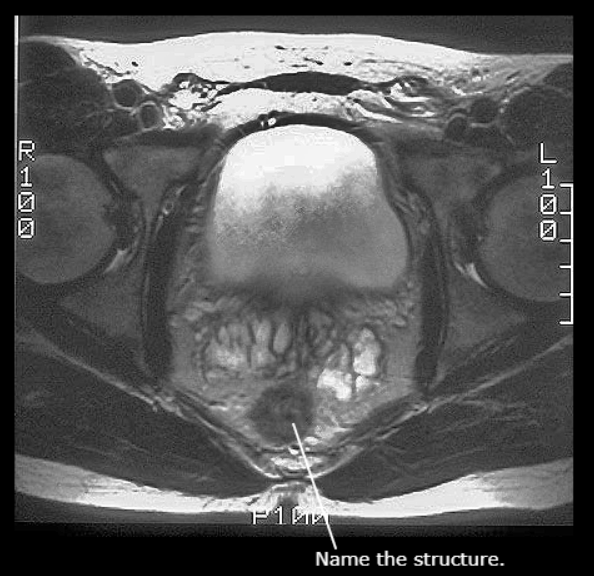

Fundus of Uterus

Pubic Symphysis

Prostatic Urethra

Urinary Bladder